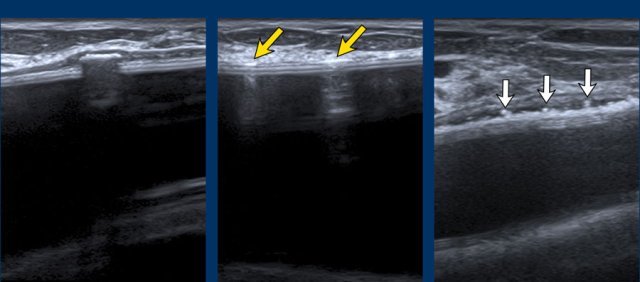

Stepladder sign

US can detect intracapsular rupture by identifying a series of horizontal echogenic straight or curvilinear lines, somewhat parallel, traversing the interior of the implant, commonly known as the “stepladder sign”.

It is important not to confuse the stepladder sign with normal prominent radial folds.

Images

More examples of the “stepladder sign”.

A. The envelope can no longer be found around the surface of the implant. The inner content is complete inhomogeneous and degenerated.

B. The envelope is collapsed (yellow arrow) and does not follow the outer envelope-capsular complex (white arrow).

There is an inhomogenous collection between the envelope and the capsule containing Silicone. .